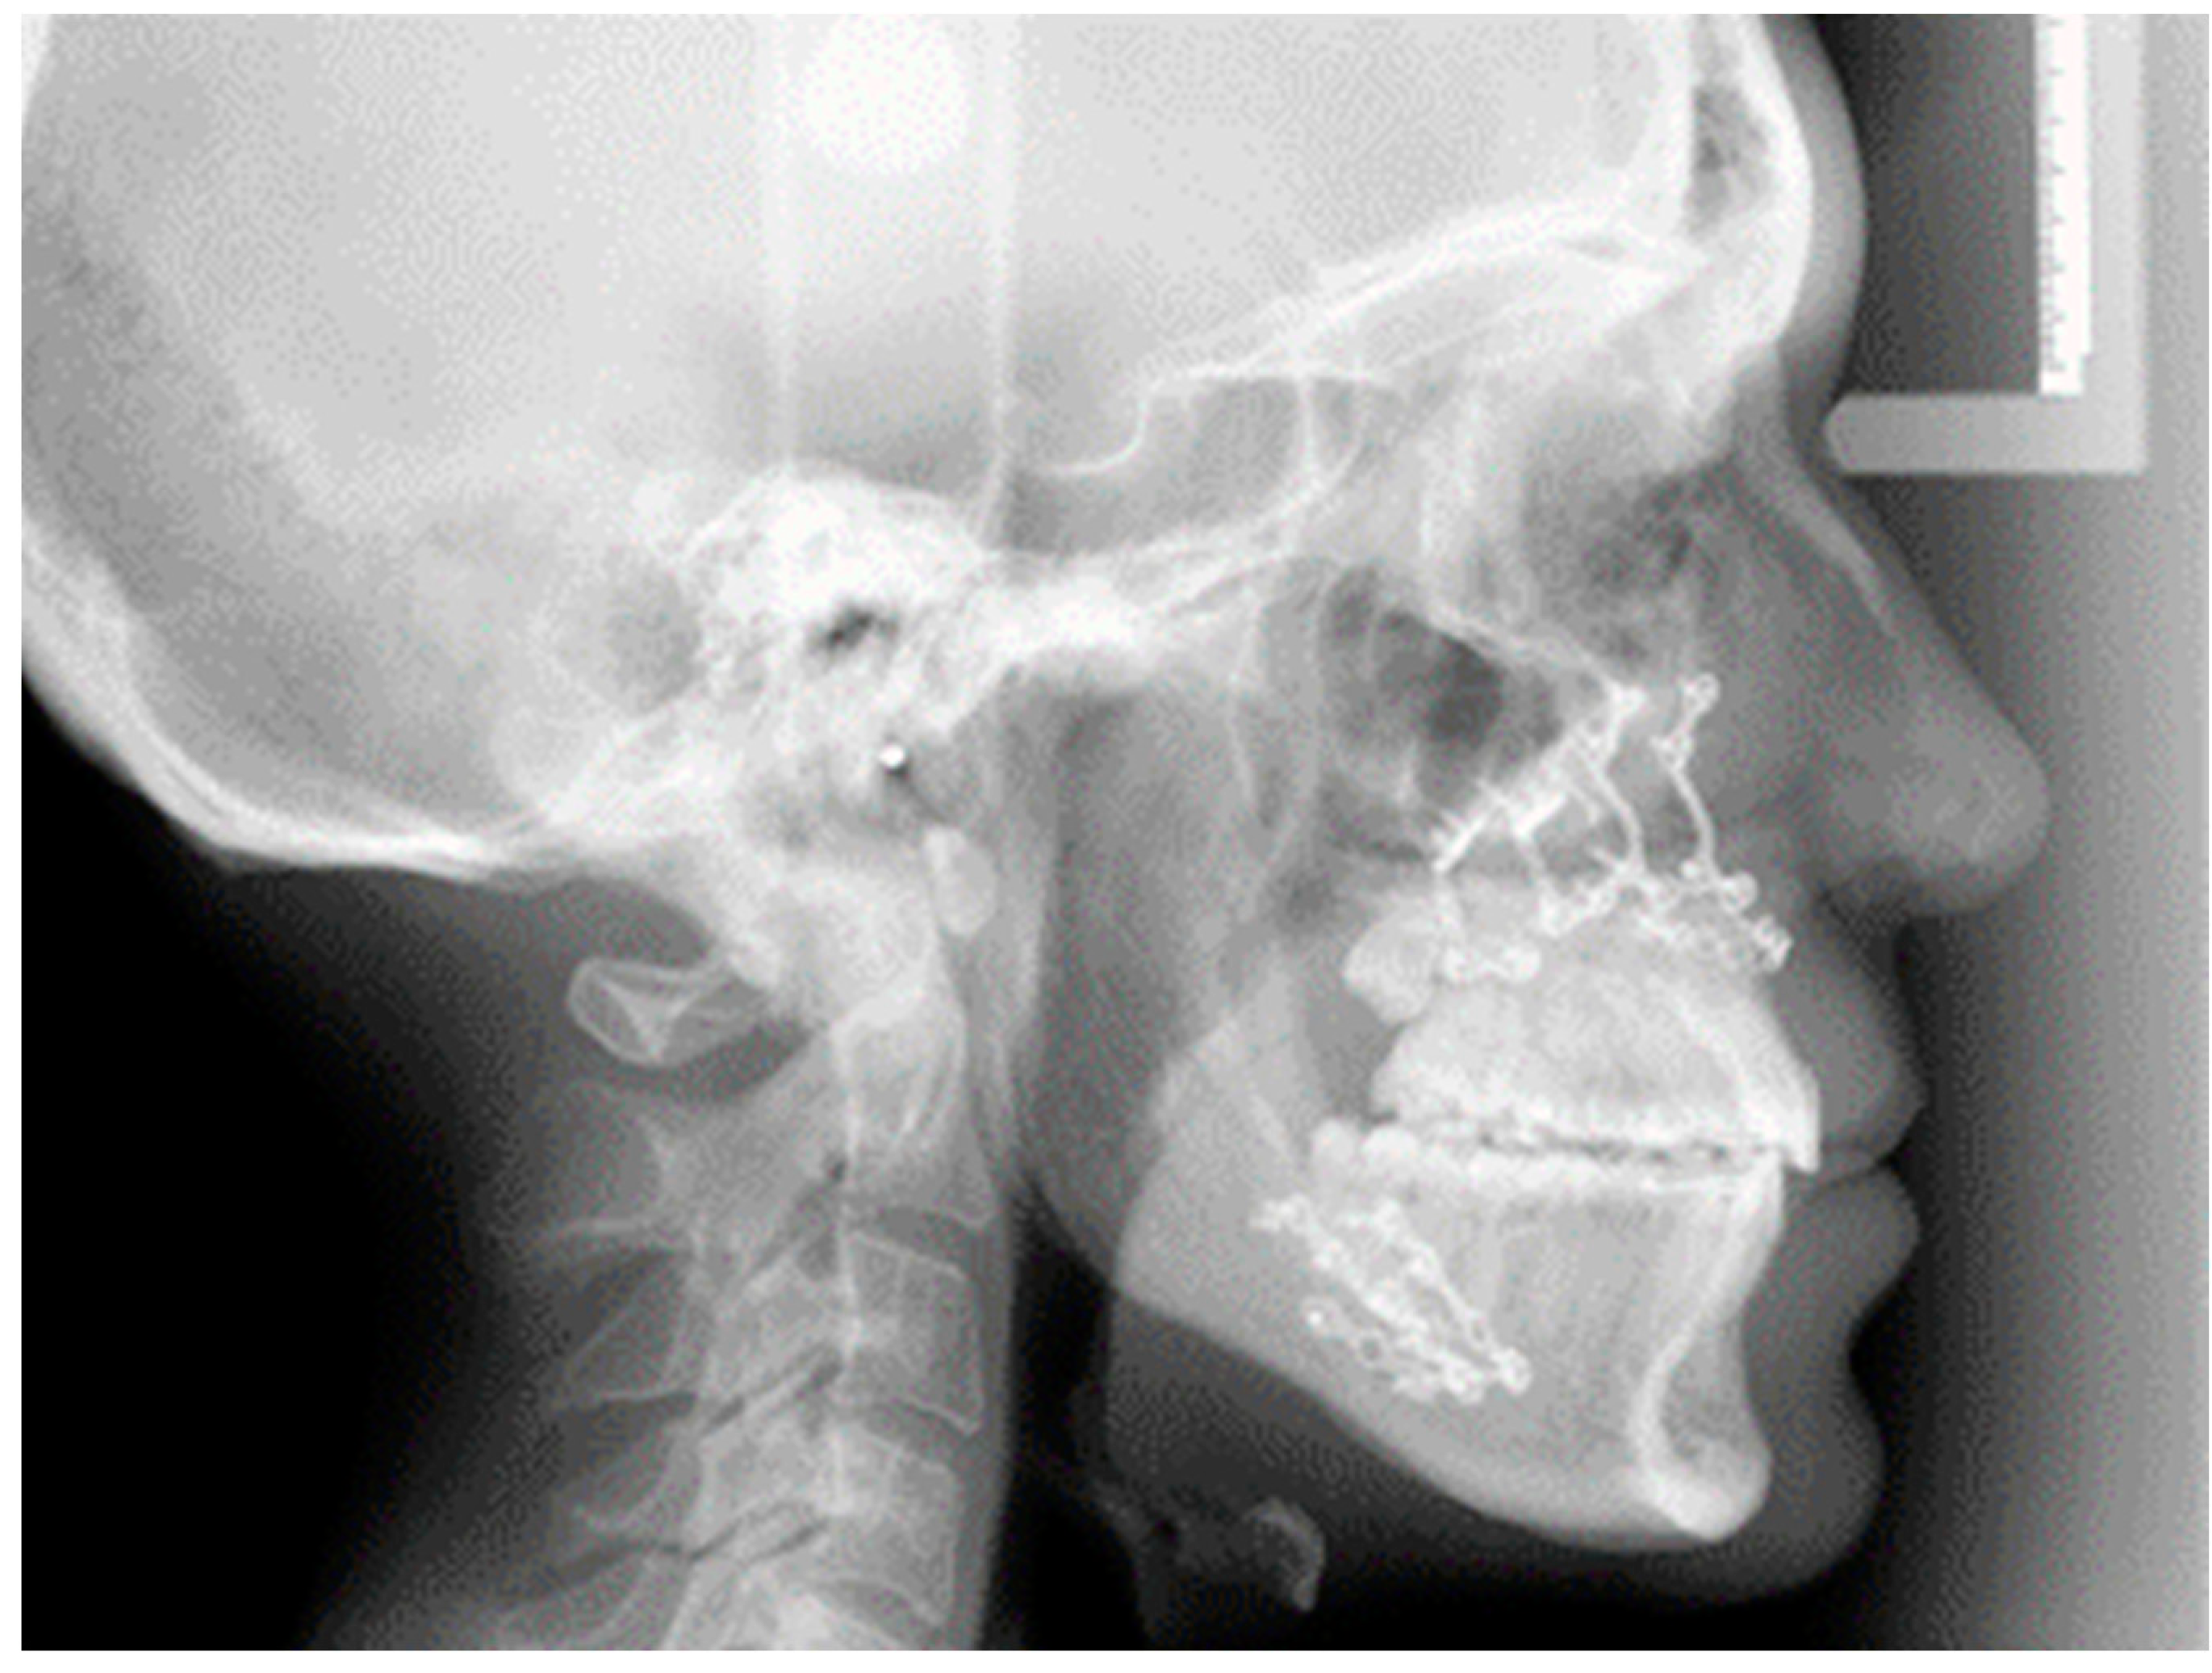

2. Materials and Method

2.1. Digital Surgical Planning